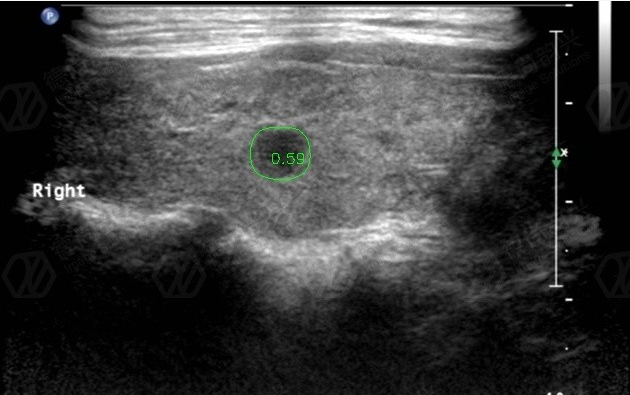

人工智能輔助診斷項目“DE-超聲機器人”落戶南京